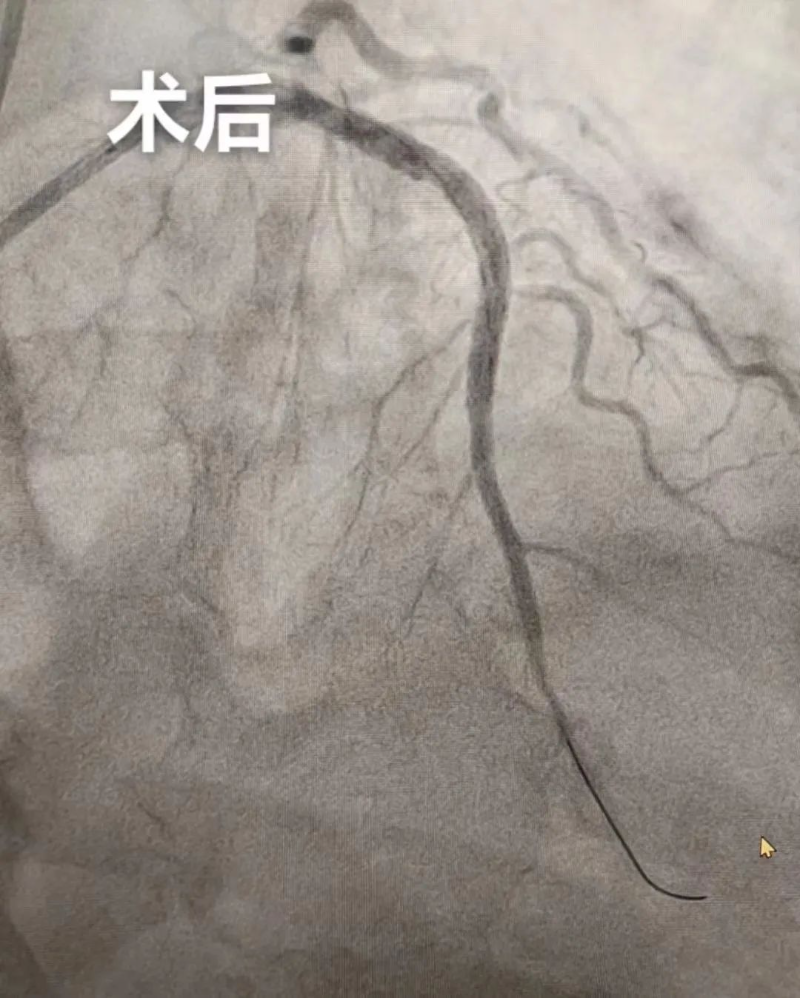

9月19日晚上,新院心血管內科為一名急性廣泛前壁心肌梗死患者行支架植入術,成功挽救了患者的生命,阻止了病情的繼續惡化,這也是我院整體搬遷至新院后的首臺介入手術,標志著新院介入室正式啟用,邁入一個新起點。

家住楊村80歲的李大爺(化名)胸口疼痛呈壓榨性,疼痛癥狀持續不能緩解。家屬送李大爺到楊僑鎮衛生院就診,心電圖結果提示廣泛前壁ST段抬高,楊僑鎮衛生院通過分級轉診微信工作群傳送心電圖,經我院心血管內科楊世映副主任醫師遠程會診,確診為急性廣泛前壁心肌梗死,建議綠色通道雙繞行急診PCI。

隨后,楊僑鎮衛生院立即護送李大爺轉診至我院,送入介入室,介入團隊快速完成急性心梗支架植入術,門球時間20分鐘。術后,李大爺轉危為安。